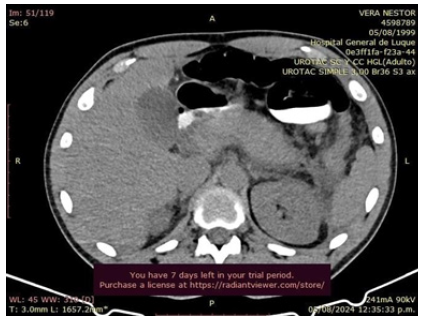

The MRCP report showed a well-distended gallbladder with thin, regular walls, with filling defects suggestive of stones. The cystic duct was appropriately implanted at the posterior margin of the proximal common bile duct. No bile duct dilatation was observed. Signs of pancreatitis with a peripancreatic collection were noted (Figure 3).

Figure 3: CRMN. Gallbladder shows absence of filling suggestive of stones. Signs of pancreatitis with peripancreatic collection.